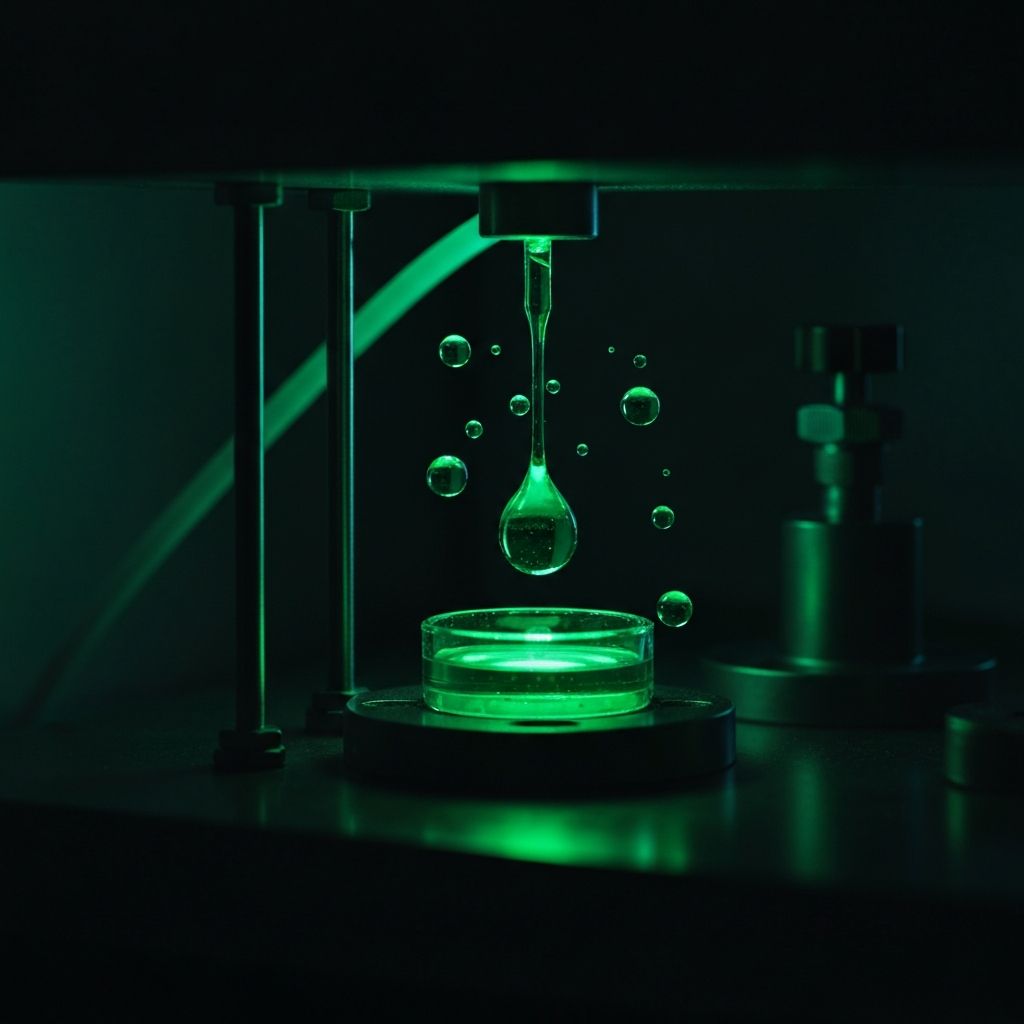

AQUASPECTR

Генерация живой водородной воды с отрицательным зарядом

ОТ ЧЕГО: Окислительный стресс — главный механизм старения и развития хронических заболеваний: сердечно-сосудистые патологии, метаболический синдром, нейродегенерация, хроническая усталость, снижение спортивной восстанавливаемости.

ДЛЯ ЧЕГО: AQUASPECTR генерирует воду, насыщенную молекулярным водородом H₂ (до 1.6 ppm) с отрицательным ОВП (−650 мВ). Молекулярный водород — самый малый и проникающий антиоксидант: достигает митохондрий, нейтрализует гидроксильный радикал (·OH) — наиболее токсичный продукт окисления. Более 1 500 клинических исследований в PubMed подтверждают эффективность при 170+ заболеваниях.

Водные ресурсы и АКВАСТАРТ

Технологии молекулярного водорода AQUASPECTR, гидрология, очистка и структурирование воды.

ИнновацииЧистая вода ТРИВИА — здоровье нации

Структурированная вода нового поколения с уникальным частотным спектром. Программа «Чистая вода ТРИВИА» — биоэнергетически активная вода артезианского происхождения с доказанными физиологическими эффектами.

ИнновацииВодородная вода AQUASPECTR — новое поколение

Растения, животные и люди состоят из отрицательно заряженной воды на 70–90%. AQUASPECTR предоставляет неиссякаемый источник «живой» воды с доказанными свойствами.